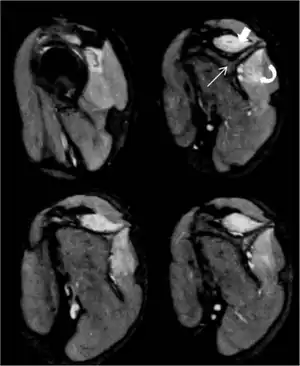

Magnetic resonance imaging shows edema in suprasinatus solid arrow and infraspinatus curved arrow muscles; scapula straight arrow

This syndrome can begin with severe shoulder or arm pain followed by weakness and numbness.[5] Those who suffer from Parsonage–Turner experience acute, sudden-onset pain radiating from the shoulder to the upper arm. Affected muscles become weak and atrophied, and in advanced cases, paralyzed. Occasionally, there will be no pain and just paralysis, and sometimes just pain, not ending in paralysis. MRI may assist in diagnosis.[7] Scapular winging is commonly seen.